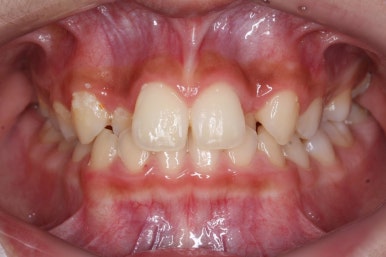

처음 내원 때의 입안 모습입니다.

영구치는 모두 맹출이 되어있었고 아랫니는 윗니에 비해 매우 가지런한 편이였습니다.

윗니 중에서도 앞니가 매우 삐뚤하고 특히 작은 앞니 양쪽 모두가 아래 앞니보다 안쪽에 들어가 있는 모습입니다.